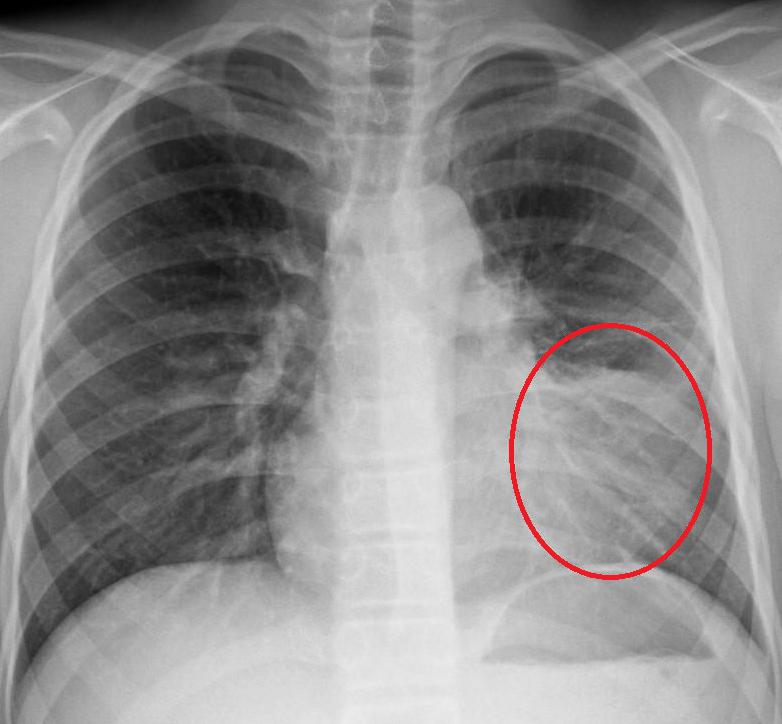

Как определить, что пневмония побеждена, если больной продолжает кашлять? Для этого необходимо сделать рентгеновский снимок легких. Иногда остаточные явления после пневмонии на рентгене наблюдаются как незначительные затемнения на легких. Их можно хорошо разглядеть на пленке.

Чтобы устранить воспалительный процесс в легких, назначается антибактериальная терапия. Процесс лечения легко контролировать с помощью рентгена. А вот бронхит как остаточное явление пневмонии на снимке можно не заметить. Это случается тогда, когда врач не имеет надлежащего опыта или рентгеновское оборудование низкого качества.

Можно увидеть остаточные явления после пневмонии на рентгене. Чтобы их не допустить, лечение антибактериальными препаратами должно продолжаться от 10 до 14 дней и никак не меньше. Кроме противовоспалительных средств, больной также должен принимать и отхаркивающие лекарства.

Но если кашель сильный и не проходит долгое время, то лучше всего обратиться за помощью к врачу. Специалист определит, насколько опасны остаточные явления пневмонии, на рентгене.

Очаговые образования в легких на рентгенограмме – распространенный синдром. Большая часть очагов на снимке провоцируется пневмонией, туберкулезом. Нельзя упускать из виду раковые образования, абсцессы. Сформировать диагноз после обнаружения очаговых теней рентгенологи не всегда могут, поэтому проводят только описание. Заключение формируется только после дополнительной диагностики – боковое, прицельные проекции, компьютерная томография, ПЭТ/КТ. По некоторым заключением можно составить альтернативное мнение с возможность предположения патологии высокой степени достоверности. Предлагаем ознакомиться с распространенными нозологиями, которые становится причиной обнаружение на рентгенограмме очагового образования правого и левого легкого, диссеминированных милиарных очагов.

Первое место по частоте среди всех очаговых образований в легких занимают пневмонии. Около 30% всех случаях обусловлены воспалением легочной ткани бактериальной или вирусной этиологии. Нозология формирует на рентгеновском снимке очаговоподобные тени с наличием специфических особенностей, позволяющих отличить пневмонические очаги от других заболеваний. Особенности очаговых образований при пневмонии на рентгенограмме: • Тень до 1 см в диаметре; • Контур неровный, нечеткий за счет воспалительной реакции; • Вокруг затемнения – усиление легочного рисунка. Диагноз не представляет сложностей при наличии на снимке описанных изменений, воспалительном характере лабораторных изменений, аускультативной картине хрипов в легких. Современные врачи говорят о повышении частоты неклассических видов пневмонии. Все чаще выявляются формы без температуры, хрипов, нормальным или сниженным количеством лейкоцитов. Единственным проявлением такого воспаления становится лишь рентгеновский синдром «очаговой тени в правом легком». Правосторонняя локализация встречается чаще, чем слева из-за особенностей анатомического строения. Справа нижний бронх расположен почти вертикально, что создает возможности для быстрого проникновения бактерий. Повальное, бесконтрольное использованием антибиотиков населением привело к формированию нечувствительности микроорганизмов к препаратам. На этом фоне наблюдается нетрадиционное течение заболевания с отсутствием температуры, выраженных лабораторных изменений.

Рентгенограмма – небольшой очаг на снимке справа при пневмонии